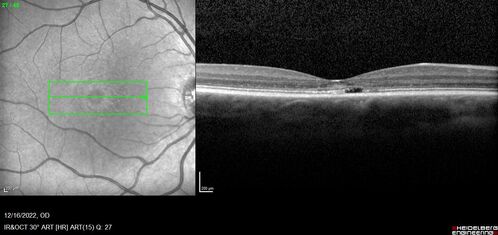

Stargardt Disease - Very Mild - 24 year old

This patient has 3 different ABCA4 mutations. His mother and sister have stargardts and his father has RP. His sisters images are also on Retinagallery.com